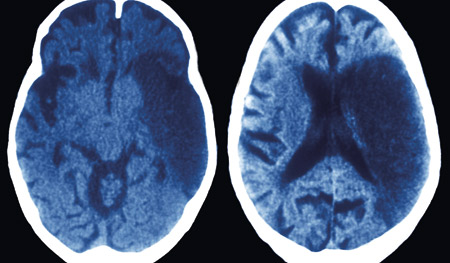

Hjerneinfarkt eller hjerneblødning?

Bildediagnostikk er helt nødvendig for å kunne skille sikkert mellom hjerneblødning og hjerneinfarkt. Det viser en metaanalyse.

Forskerne gjennomgikk 19 prospektive studier med til sammen 6 438 pasienter (1). Koma, nakkestivhet, krampeanfall, hodepine, oppkast og diastolisk blodtrykk > 110 mm Hg er alle faktorer som enkeltvis er assosiert med signifikant høyere sannsynlighet for hjerneblødning.

Systematisk sammenstilling av slike symptomer og tegn vil likevel bare øke posttestsannsynligheten for at det foreligger hjerneblødning med 50 %. Interessant nok viser en av grunnlagsstudiene at den samme økning i diagnostisk presisjon kan oppnås ved å legge til grunn et udefinert og usystematisk «klinisk inntrykk» av hvorvidt det foreligger hjerneblødning eller hjerneinfarkt, noe som tyder på at erfarne klinikere gjør andre og mer komplekse vurderinger enn det som er mulig å måle i slike studier.

– Selv om artikkelens tittel indikerer det motsatte, viser analysene at det på klinisk grunnlag ikke er mulig å differensiere mellom infarkt og blødning, sier Lars Thomassen, professor ved Nevrologisk avdeling, Haukeland universitetssykehus.

– I Bergen Stroke Registry, som omfatter 1 101 pasienter, har bare 20 % så alvorlige utfall at man kan anta forhøyet intrakranialt trykk. Siden blødninger utgjør ca. 10 % av alle slag, vil tegn til forhøyet intrakranialt trykk foreligge hos ca. 2 % av norske slagpasienter. Både hos disse 2 % og de øvrige 98 % er bildediagnostikk absolutt nødvendig, sier Thomassen.